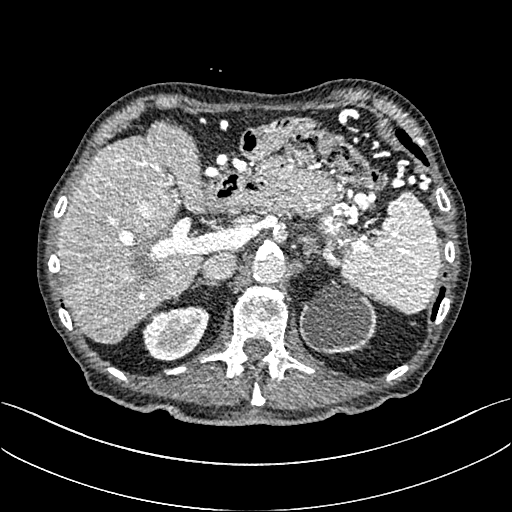

To demonstrate the effectiveness of the proposed network, we perform the qualitative comparisons over three representative abdominal images presented in Figs. 3, 5 and 7. For better evaluations of the image quality with different denoising models, zoomed regions-of-interest (ROIs) are marked by red rectangles and shown in Figs. 4, 6 and 8 respectively. Note that all results from different denoising models focus on two aspects: content restoration and noise-reduction. All CT images in axial view are displayed in the angiography window [-160, 240]HU.

The real NDCT images and corresponding LDCT images are presented in Figs. 3a and 3b. As observed, there are distinctions between ground truth (NDCT) images and LDCT images. Figs. 3a and 7a show the lesions/metastasis. Fig. 5a presents focal fatty sparing/focal fat. In Figs. 4a, 6a and 8a, these lesions can be clearly observed in NDCT images; in contrast, from Figs. 4b, 6b, and 8b, it can be seen that the original LDCT image is noisy, and lacks structural features for task-based clinical diagnosis. All adopted denoising models suppress noise to some extent.